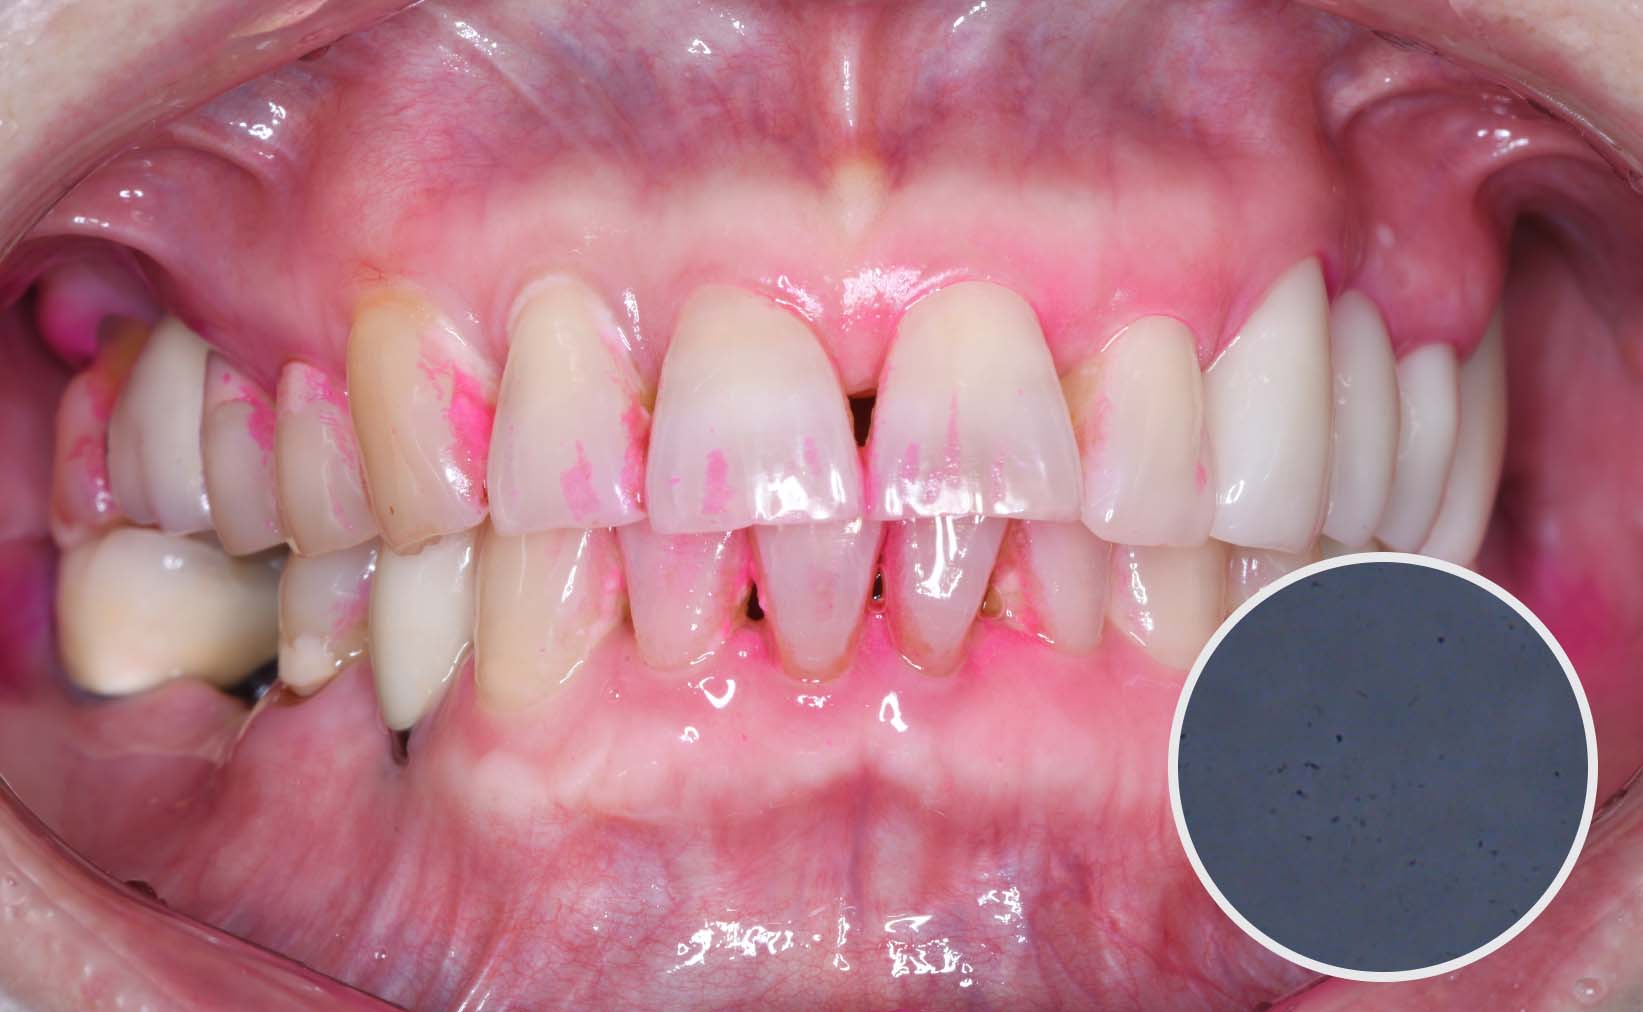

[예방치료] 세종치과 TOC4U

치료전 : 2023-07-10

치료후 : 2023-08-30

세종치과 예방 관리

치아 건강을 방해하는 원인을 단계별 구강검진을 통해 알아보고

예방 전담 의료진의 1:1 맞춤 교육까지 진행하는 세종치과의 예방 프로그램을 시작해보세요.